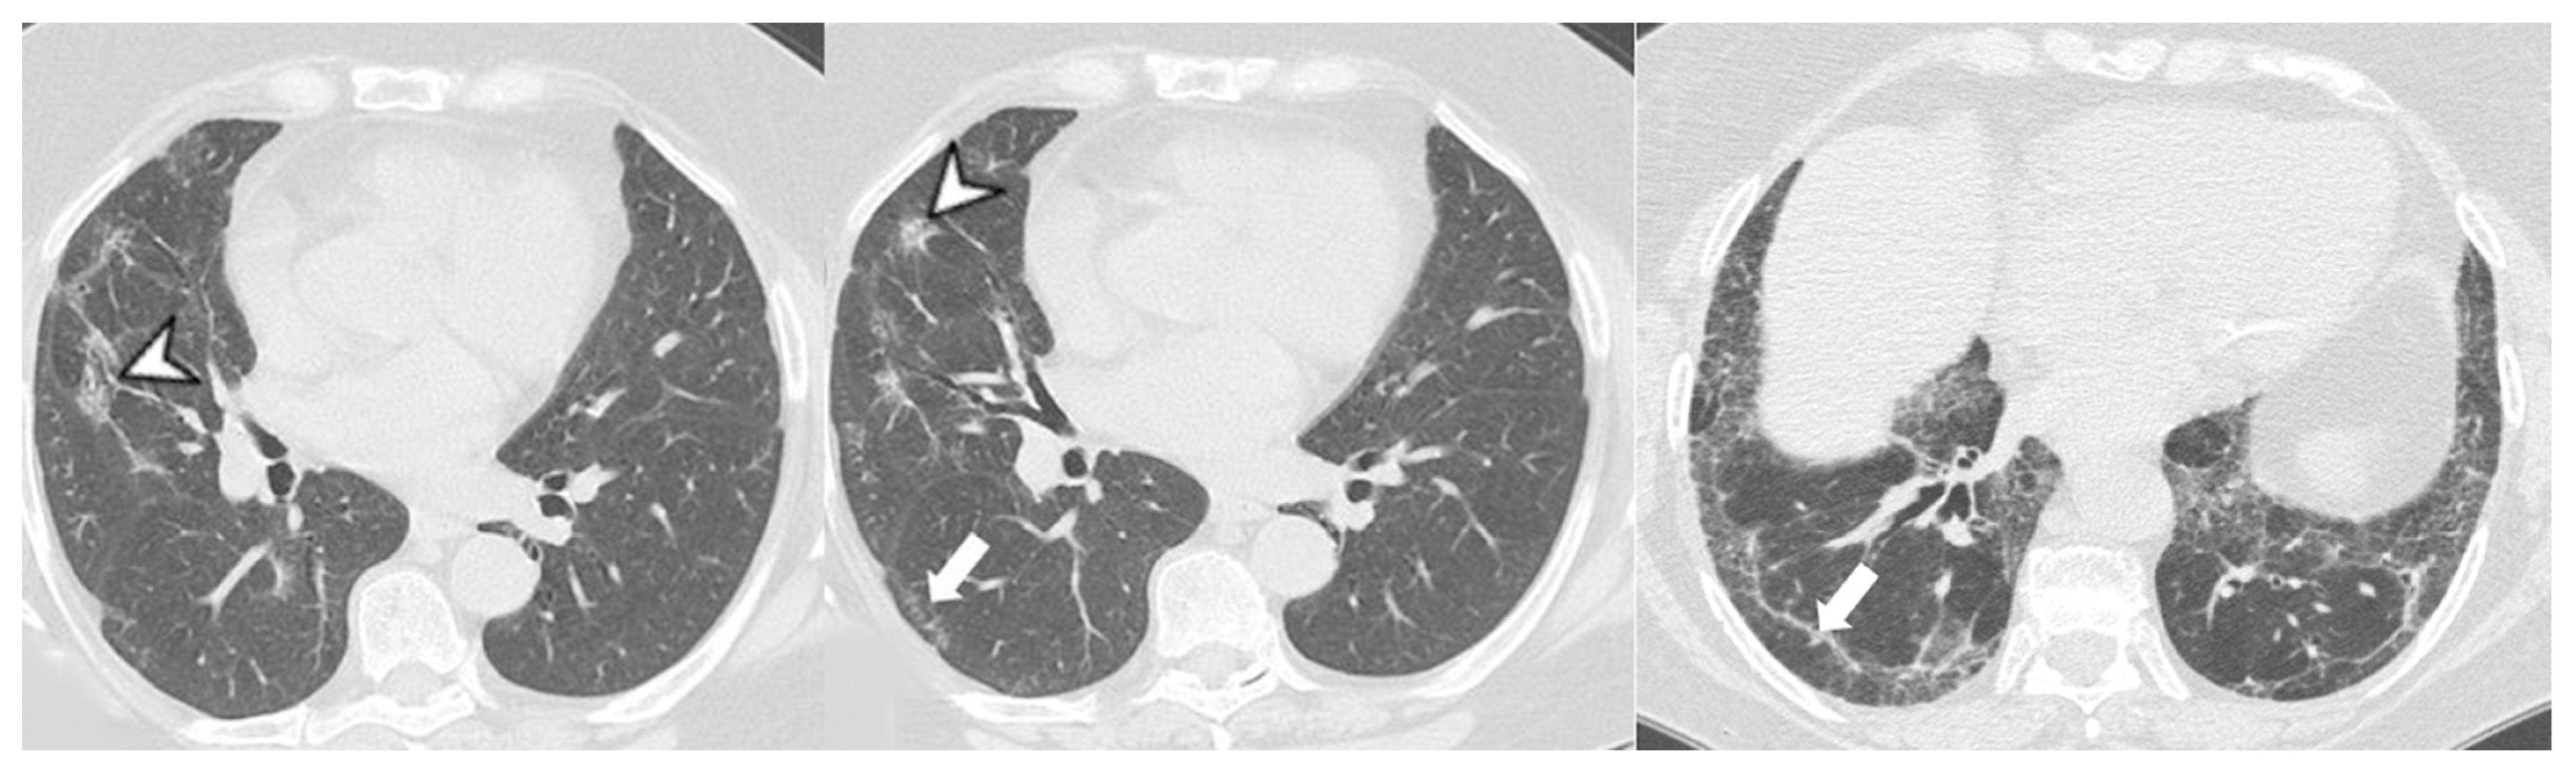

4.2.2. HRCT Findings of Patients with Anti-MDA-5 Abs

| Lesions | GGO, reticulations, consolidations | consolidations, GGOs | |

| Distribution | Homogeneous; lower lung lobes, along bronchovascular bundles and lung periphery; loss of volume of lower lobes | Patchy; peripheral lower lobes or along the bronchovascular bundles | |

| CT pattern | NSIP OP NSIP-OP UIP DAD-unclassifiable | 50% 20% 25% 10% +/− | 20% 50% 25% <5% ++ |